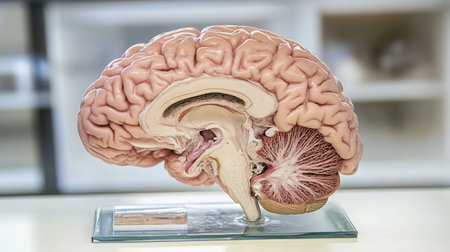

This detailed anatomical model of the human brain showcases its complex structure, perfect for educational settings or medical displays, enhancing learning and understanding.

This image features a detailed human brain model, showcasing the vascular structure, set in a modern laboratory environment, ideal for educational materials.

This detailed cross-section of the human brain illustrates its anatomical features, making it ideal for educational purposes in neuroscience and medicine.

This detailed model showcases human brain anatomy, perfect for educational purposes. Ideal for classrooms, medical training, and scientific research.

An educational scene featuring a human brain cross-section with labeled parts, alongside medical charts and anatomical references for a classroom setting.

This high-quality image features an anatomically accurate brain model, showcasing intricate vascular structures and the spinal cord, ideal for educational use.

This close-up photo captures the intricate details and structures of a human brain, Cross-sectional image of a human brain, AI Generated

This anatomical model of the human brain showcases detailed features and structures, making it ideal for education and scientific study in various fields.

This detailed human brain model showcases various regions and structures, ideal for educational purposes in neuroscience and psychology, emphasizing anatomical clarity.

An educational diagram of the human brain with major parts and functions labeled, set against a simple white background for clear, informative presentation.

This detailed model of a human brain showcases intricate features of neuroanatomy. Ideal for educational and scientific purposes, it highlights brain structure for study and research.

This anatomical model of the human brain provides a detailed view of its structures. Ideal for educational purposes, it supports learning in biology and neuroscience.

An educational scene featuring a human brain cross-section with labeled parts, alongside medical charts and anatomical references for a classroom setting.

An educational scene featuring a human brain cross-section with labeled parts, alongside medical charts and anatomical references for a classroom setting.